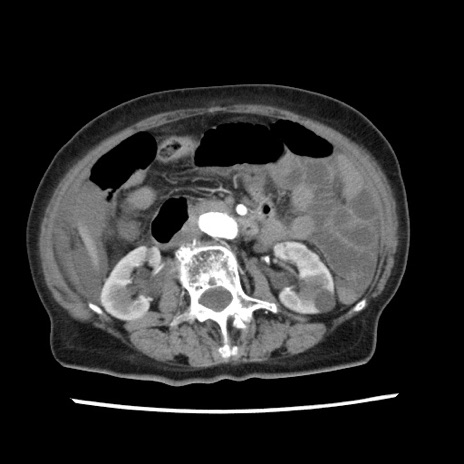

冠状断像

【症例】80歳代女性

【主訴】腹痛

【現病歴】8時間前から腹痛あり来院。

【既往歴】糖尿病、脂質異常症、子宮体癌にて子宮全摘術

【身体所見】意識清明・会話良好だが腹痛で苦悶様、全腹部にわたって反跳痛と圧痛あり

【データ】WBC 13600、CRP 0.14、LDH 224、CK 90